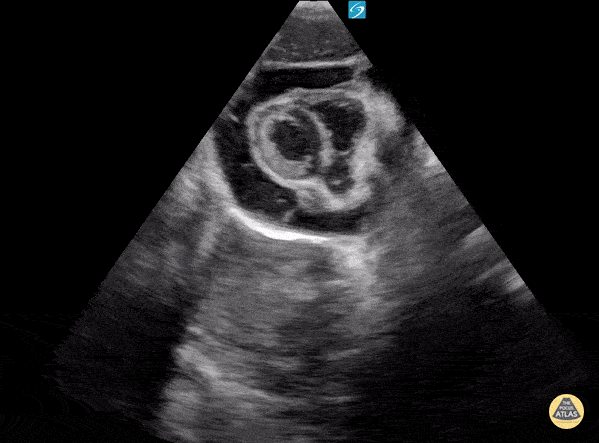

3 yo with known post viral pericardial effusion who comes to the ED with acute onset shortness of breath. POCUS shows effusion. Cardiology consulted and performed a pericardiocentesis in the cath lab. Contributor: David Lowe, MD Nicklaus Children's Hospital